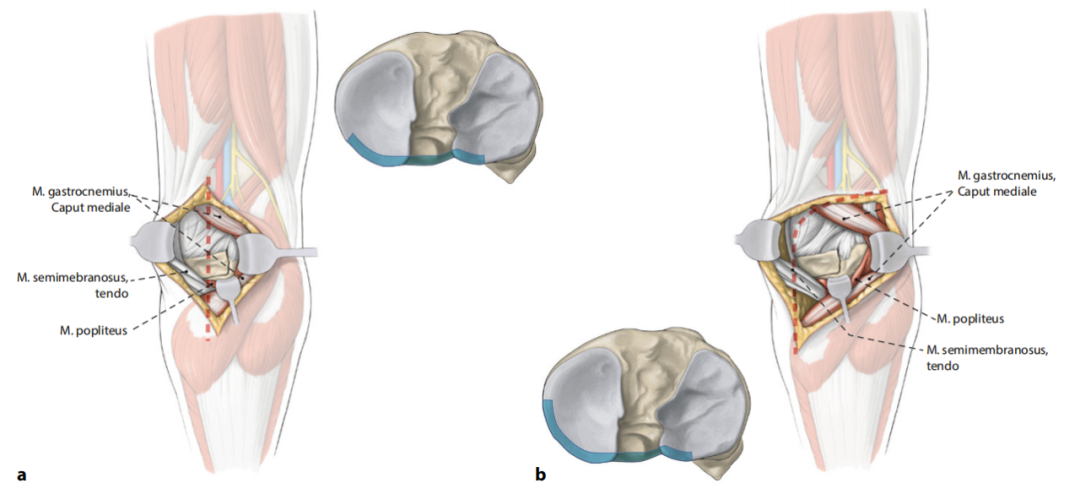

Hoekstra等学者提出的扩展三柱分型系统——作为对Luo等2011年三柱理论的进阶发展——已被证实适用于需手术治疗且具备CT影像的复杂胫骨平台骨折病例。该分型将后侧柱界定至胫腓近端关节背侧,这一解剖学定义对制定治疗策略及选择手术入路具有重要指导价值(图2)。其核心原则是根据骨折累及柱体结构的具体情况,选择既能充分显露关节面、又能有效稳定受累柱体的手术入路。研究表明,该模型在骨折治疗规划中展现出显著优势,且不同观察者间分型判定具有高度一致性。下文将基于此分型框架,系统阐述各类手术技巧与治疗策略。

图2:根据Luo等人(2011年)提出并经Hoekstra团队修订的三柱理论模型,在最新版本中进行了以下重要调整:原归属于后柱的近端腓距关节区域现被重新划归至外侧柱。这一分类调整基于新型手术入路的可行性研究,学者们论证了通过扩展前外侧入路,配合角度稳定型内固定装置即可完成该区域的治疗,从而无需再额外建立传统后侧手术入路。